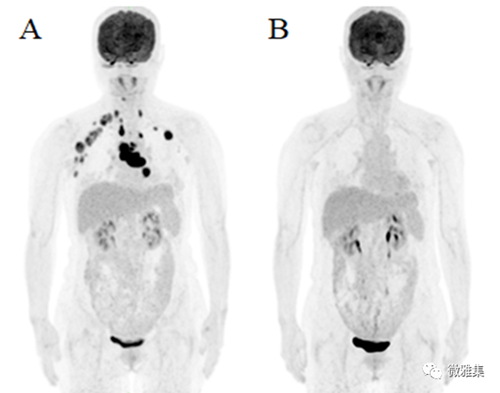

女,21岁,弥漫大B细胞淋巴瘤,A.治疗前PET全身MIP图,示双颈深、锁骨、腋窝及左肺门、纵隔多发肿大淋巴结,代谢增高(Ⅱ期);B.4程化疗后PET全身MIP图,原病灶消失,评价为完全缓解CR,Deauville score,DS(见表4)评分为1分